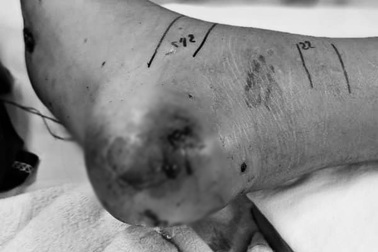

Thầy lang cắt lể “máu độc” ở chân, bệnh nhi suýt mất mạngThấy chân của con bị sưng tấy kèm đau nhức phụ huynh đã đưa đi nhờ thầy lang cắt lể, nặn “máu độc”. Hơn 1 tuần sau chân bệnh nhi bị sưng tấy, nhiễm trùng, hoại tử phải nhập viện cấp cứu.

Phải tháo khớp 5 ngón chân vì hoại tử do cắt lểBị đau cơ đùi trái, em T. được gia đình đưa đi cắt lể để thoát máu dơ. Hậu quả từ những nhát dao lam nham nhở khiến bệnh nhân bị sốc nhiễm trùng, năm ngón chân hoại tử tím đen buộc phải tháo khớp.